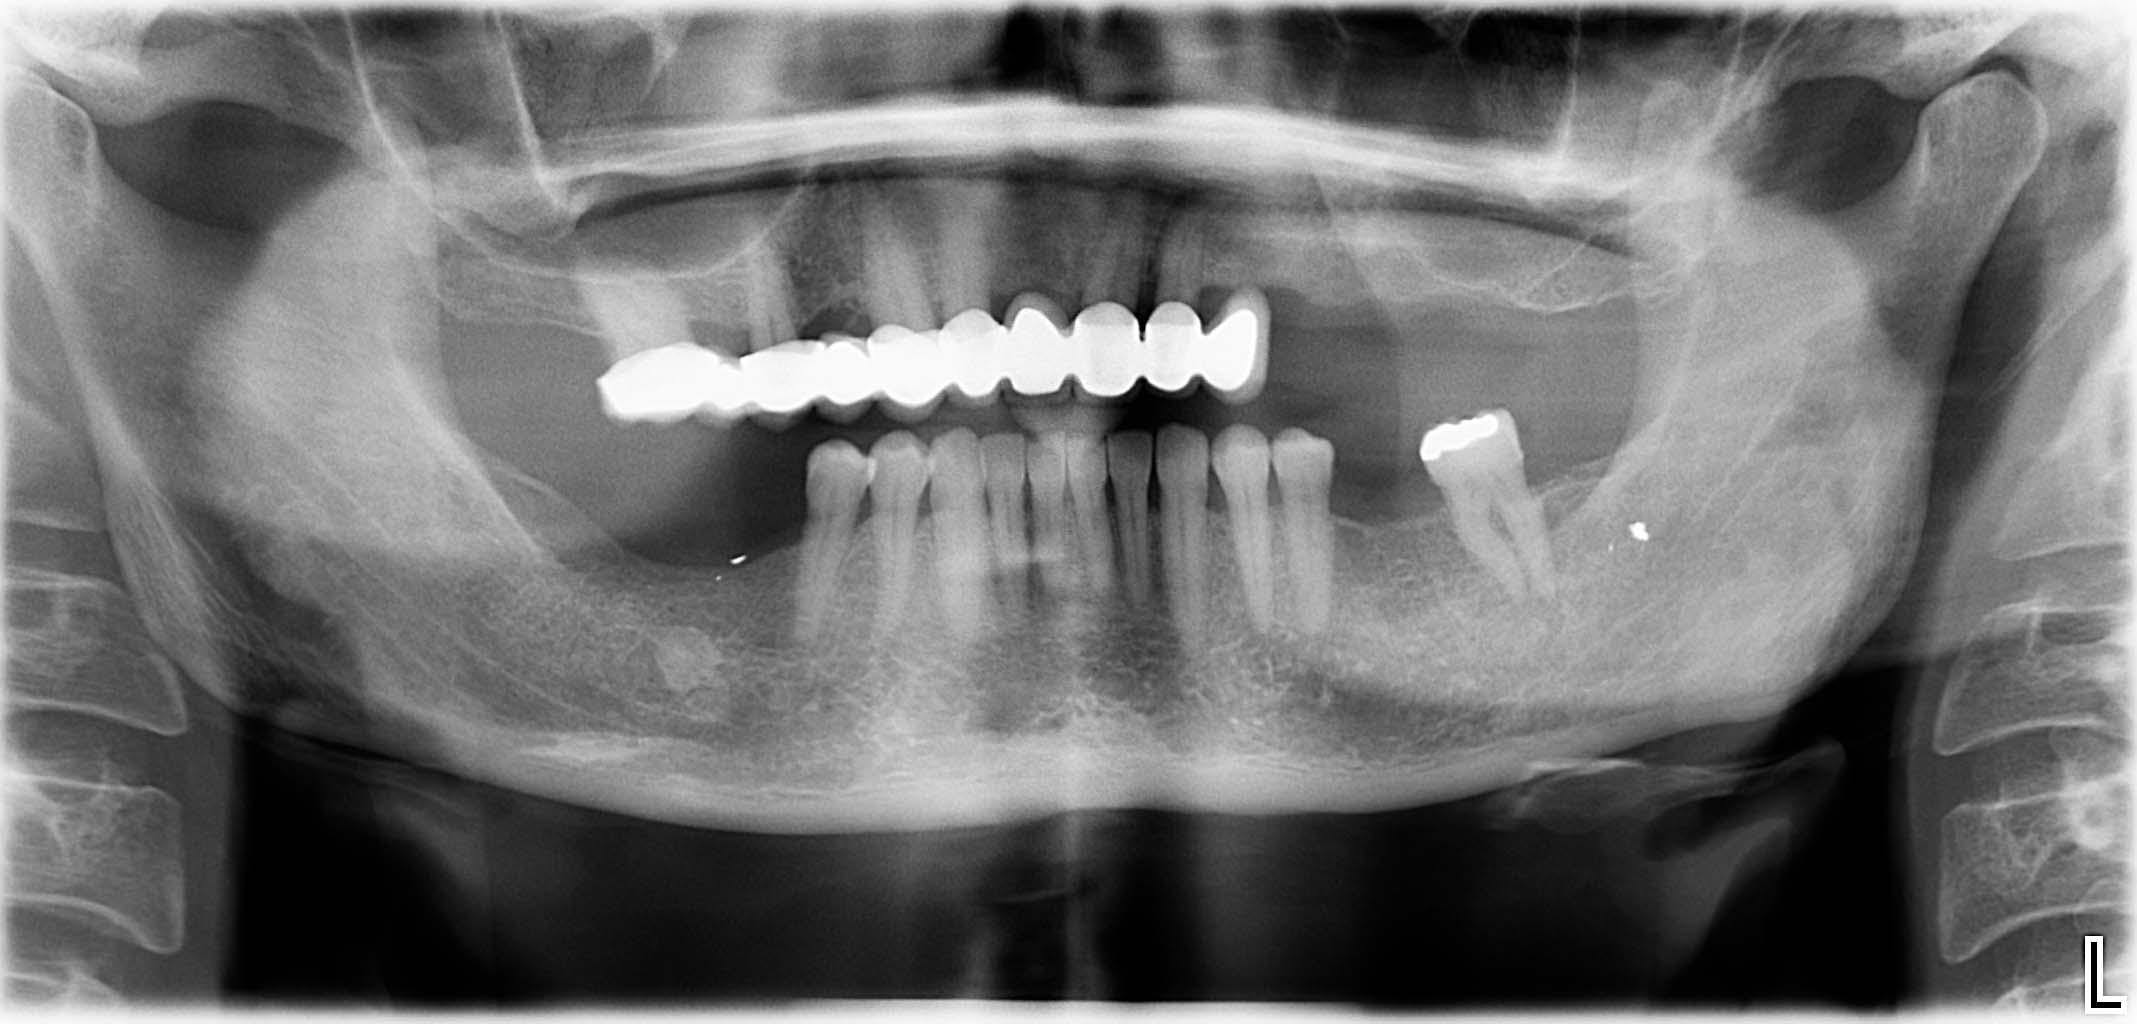

Ausgangssituation: Zahn 36 mit apikaler Beherdung, nicht erhaltungswürdig

Erfolgreich implantierte Patientenfälle (klinische Fotos)